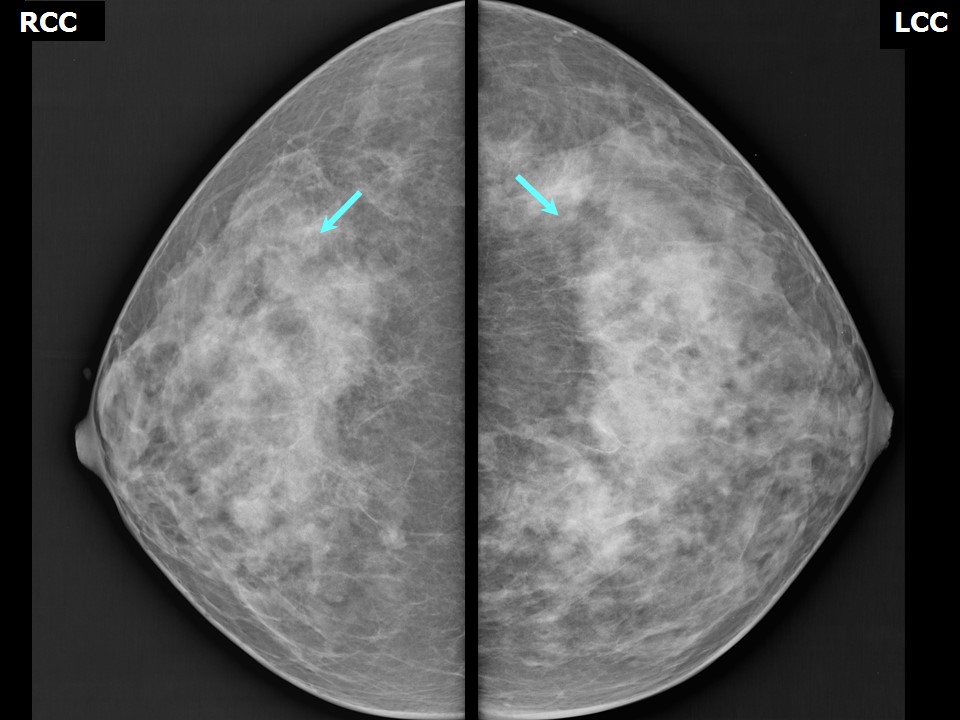

Что такое маммография: важность, процесс и результаты